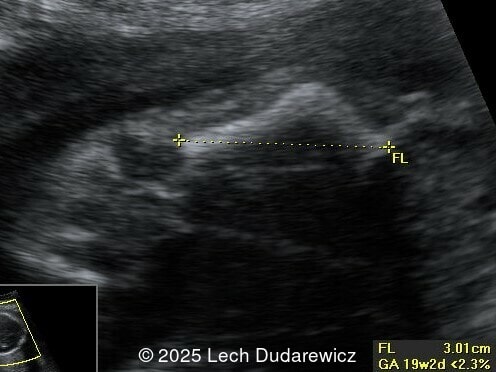

Ultrasound revealed a single live fetus with 46,XY karyotype. Biometric measurements demonstrated discrepancies with the femur and tibia length lagging significantly at 19 weeks and notable shortening and bowing of the femur, tibia, and fibula. The findings were consistent with skeletal dysplasia.

Prenatal ultrasound is a crucial tool for early diagnosis, enabling appropriate counseling and perinatal management of campomelic dysplasia. Key skeletal abnormalities include significant shortening and bowing of long bones, particularly the femur and tibia. In a study by Mansour et al, the lower extremities are primarily involved with minimal bowing of the humerus, ulna, and radius. Bowing often presents with associated angulation, giving rise to the term "campomelia," meaning bent limbs in Greek. Hypoplastic iliac bones and scapulae are hallmark features, while rib anomalies such as deformities or reduced number, typically 11 pairs, may also be observed. Additionally, the chest may be narrow and bell-shaped. Cervical spine abnormalities, including excessive lordosis or kyphosis, are often present and may contribute to postnatal respiratory complications. These findings are important for risk stratification and delivery planning.